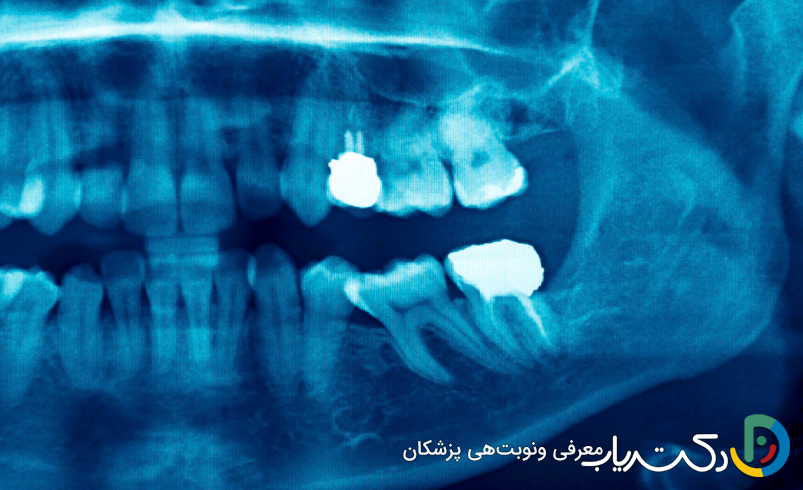

- رادیوگرافی پریآپیکال: این عکس اشعه ایکس کوچک، تصویر کاملی از تاج، ریشه و استخوان اطراف آن ارائه میدهد. وجود یک ناحیهی تیره (رادیولوسنت) در نوک ریشه، نشانهی تحلیل رفتن استخوان به دلیل واکنش دفاعی بدن در برابر عفونت است. این تصویر همچنین میتواند عمق پوسیدگی یا وجود شکستگی را مشخص کند.

- عفونت مزمن بدون درد: گاهی عفونت در انتهای ریشه به صورت مزمن و بدون درد باقی میماند و تنها در رادیوگرافی مشخص میشود. این کانون عفونی خاموش میتواند هر لحظه فعال شده یا به تخریب تدریجی استخوان ادامه دهد و باید درمان شود.